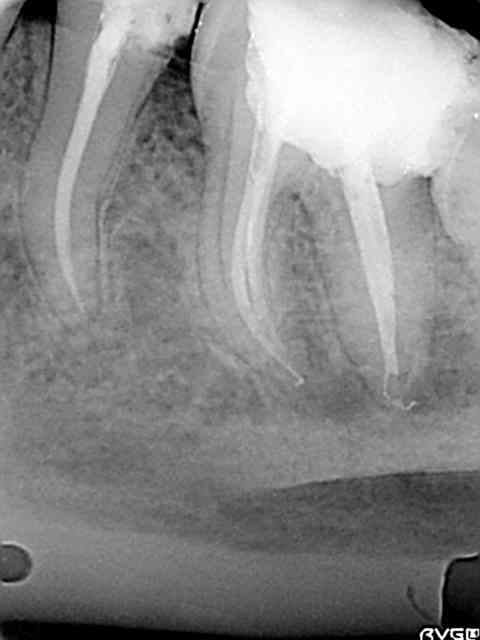

Une petite de ce matin et une plus ancienne, toutes les deux avec la même "recette".

Vous remarquerez en zoomant sur celle de ce matin comme le matériau a bien "squirté" en mésial. Devant de tels résultats, je ne vois pas pourquoi j'irai m'emmerder avec un system B...

Cematin yrjkt7 - Eugenol

Plusvieux swdvep - Eugenol